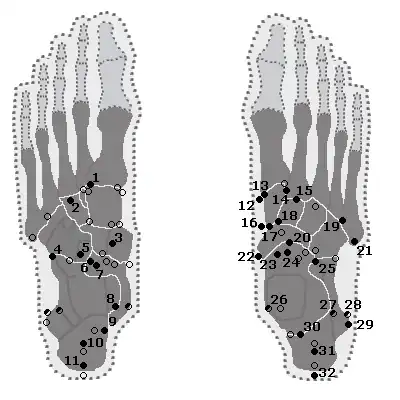

Foot

| Bone | Prevalence[17] |

|---|---|

| Sesamoid bones | |

| Sesamoids at the metatarsophalangeal (MTP) joint of the great toe | Always present |

| Sesamoid of the second metatarsal | 0.4% |

| Sesamoid of the third metatarsal | 0.2% |

| Sesamoid of the fourth metatarsal | 0.1% |

| Sesamoids of the fifth metatarsal | 4.3% |

| Sesamoid of the interphalangeal (IP) joint of the great toe | 2–13% |

| Ossicles | |

| Os trigonum (not visible in this dorsoplantar projection) | 7–25% |

| Os peroneum | Up to 26% |

| Accessory navicular | 2–21% |

| Os intermetatarseum | 1–13% |

| Os supranaviculare, also called the talonavicular bone | 1.0–3.5% |

| Os calcaneus secundarium | 0.6–7% |

| Os supratalare | 0.2–2.4% |

| Os vesalianum | 0.1–1% |

| Os talotibiale | 0.5% |